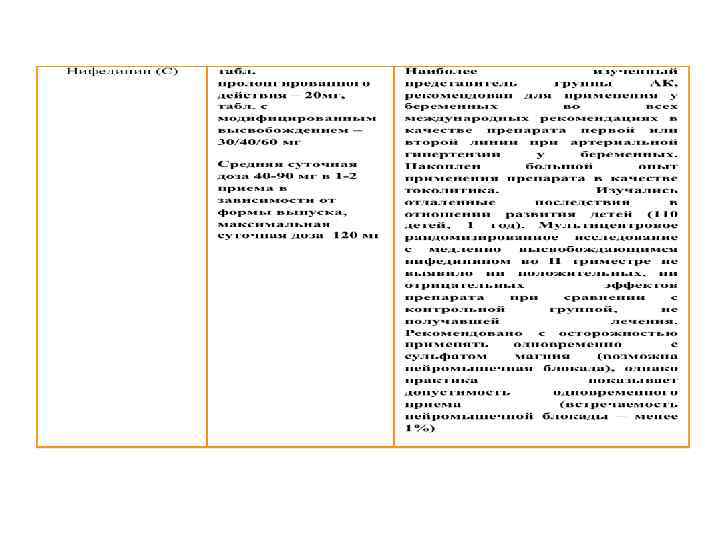

АГ ПРИ БЕРЕМЕННОСТИ Антигипертензивные препараты, применяемые для лечения АГ в период беременности

АГ ПРИ БЕРЕМЕННОСТИ Антигипертензивные препараты, применяемые для лечения АГ в период беременности